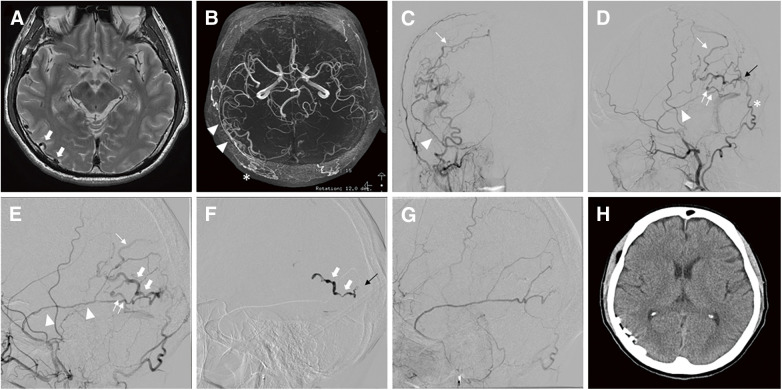

Abstract Image